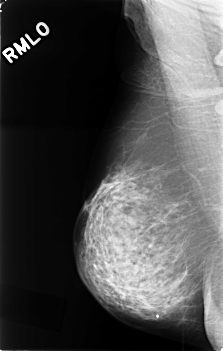

C_0419_1.RIGHT_MLO

C_0419_1.RIGHT_CC

RIGHT_CC LINES 4552 PIXELS_PER_LINE 2912 BITS_PER_PIXEL 12 RESOLUTION 50 NON_OVERLAY

RIGHT_MLO LINES 4560 PIXELS_PER_LINE 2888 BITS_PER_PIXEL 12 RESOLUTION 50 NON_OVERLAY